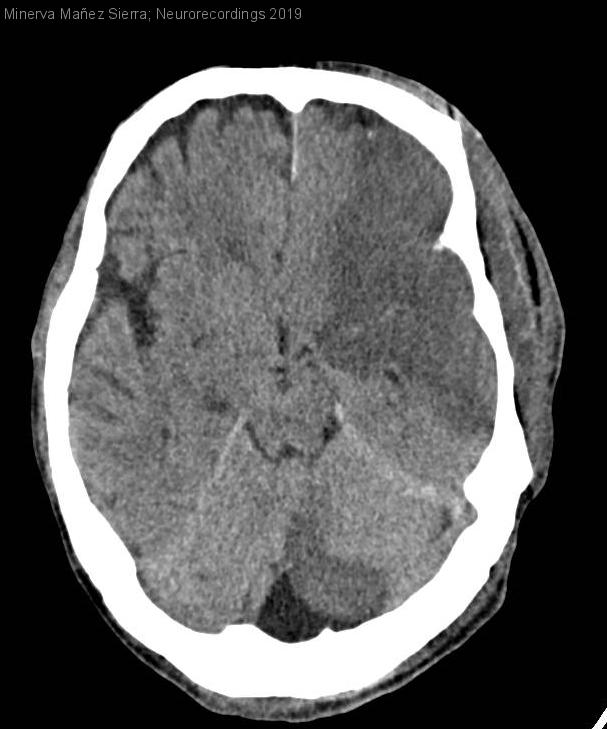

Hombre | 62 años

Diagnóstico final: Mucormicosis rinocerebral

Antecedentes: DM II y pancreatitis. Ingresado 39 días en la Unidad de Reanimación tras el postoperatorio de resección pancreática.

El paciente presenta dificultad en la movilidad de OI y pérdida de visión. La semana previa el...